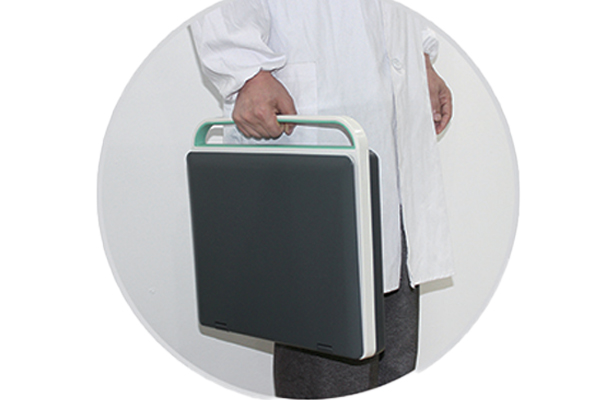

Laptop Color Doppler RK-C5N

- Laptop-style design, highly portable

- 15-inch LCD screen

The RK-C5N is a color Doppler ultrasound diagnostic system with a laptop-style design. It integrates high-performance ultrasound imaging technology in a compact and lightweight body, balancing portability with clinical diagnostic needs, and is suitable for multiple departments and various application scenarios.

-Overall size: 362mmx340mmx60mm

-Built-in battery: work 3 hours

-Total weight: 4Kg